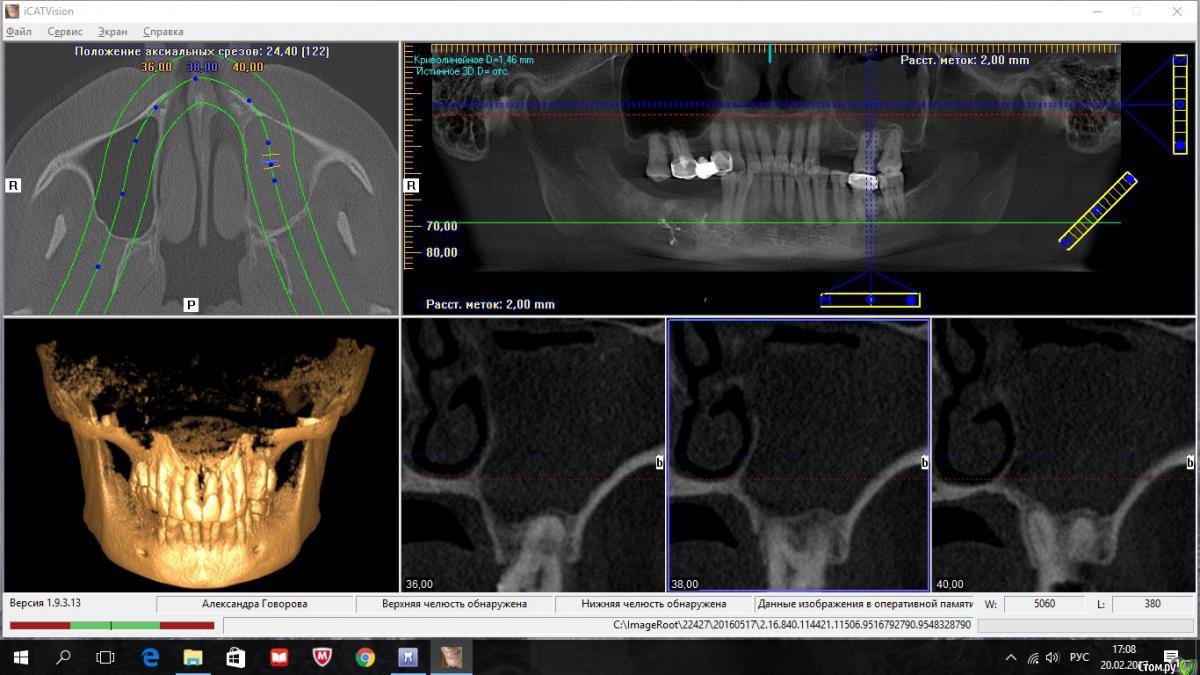

kriokov Опубликовано 20 февраля, 2017 Поделиться Опубликовано 20 февраля, 2017 пациентка 56 лет Радикальная гайморотомия в чло в сентябре 16.Удален 16. клкт до экзекуции клкт спустя месяц клкт примерно через полгода 2 Ссылка на комментарий

kriokov Опубликовано 20 февраля, 2017 Автор Поделиться Опубликовано 20 февраля, 2017 А разве Колдуэлл-Люк тут сильно виноват?не знаю, смотря что кто видит на снимках. Изначально--клиники синусита не было, смотрел пациентку на предмет иплантации во 2 сегменте, увидел рентгенологически тень с куполом в пазухе слева, 26 был живой на тот момент, отправил к лорикам, лорики в чло, кафедральные посмотрели- отпунктировали, вроде как получили кистозное наше содержимое. Соперировали.Посмотрел ее через месяц после гайморотомии. Нос дышал, чувствительность выпала, парус во рту по своду, но не критично. Решил подождать 6 мес.И вот сейчас картина -- клиники гайморита нет, дышит. Чувствительности нет, не восстановилась. По своду понятно- все как было. А вот рентгенологически картинка интересная-- там где не закрывалось латеральное окно, мягкие ткани туда и ввалились (наверное что на подобие рубцовых тканей), киста судя по всему была, как раз почти по верхней границе купола идет рост новообразованной кости. Кость по высоте 10-12 мм в обл 24 , 25, 26. Кто виноват (Колдуэлл или Пушкин) мне по барабану, я не эксперт, и не кафедральный. Думаю, если бы была возможность латеральное окно сеткой или мембраной перекрыть, пролапса мягких тканей внутрь не было бы. Ну и из разряда экзотики-- можно и на одном столе отработать члх и лорику. ИМХО 2 Ссылка на комментарий

kriokov Опубликовано 22 февраля, 2017 Автор Поделиться Опубликовано 22 февраля, 2017 вопрос основной как работать дальше с пациенткой. 1. носовое дыхание свободное2. естественное соустье работает, дырка в нижнем носовом тоже не заросла3. лор посмотрел -- дал заключение, что это не та патология, которую ЛОРики пользуют4. болты вкрутить- не вопрос, как понимаетеЧего делать с дырой?Варианты -- 1. соперировать, -- убрать мягкие ткани аккуратно из пазухи, поставить или фольгу или сетку-- окно то закрою конечно, заоодно гляну чего с подглазничным, на кт отверстия не видать , или снесено, или просто не визуализируется. НО , но, но- останется имеющаяся контрапертура в нижний носовой. Через год , полтора, может появиться симптоматика , как у пациентов после радикальной2. не трогать ничего, поставить болты.Буду говорить с пациенткой Ссылка на комментарий